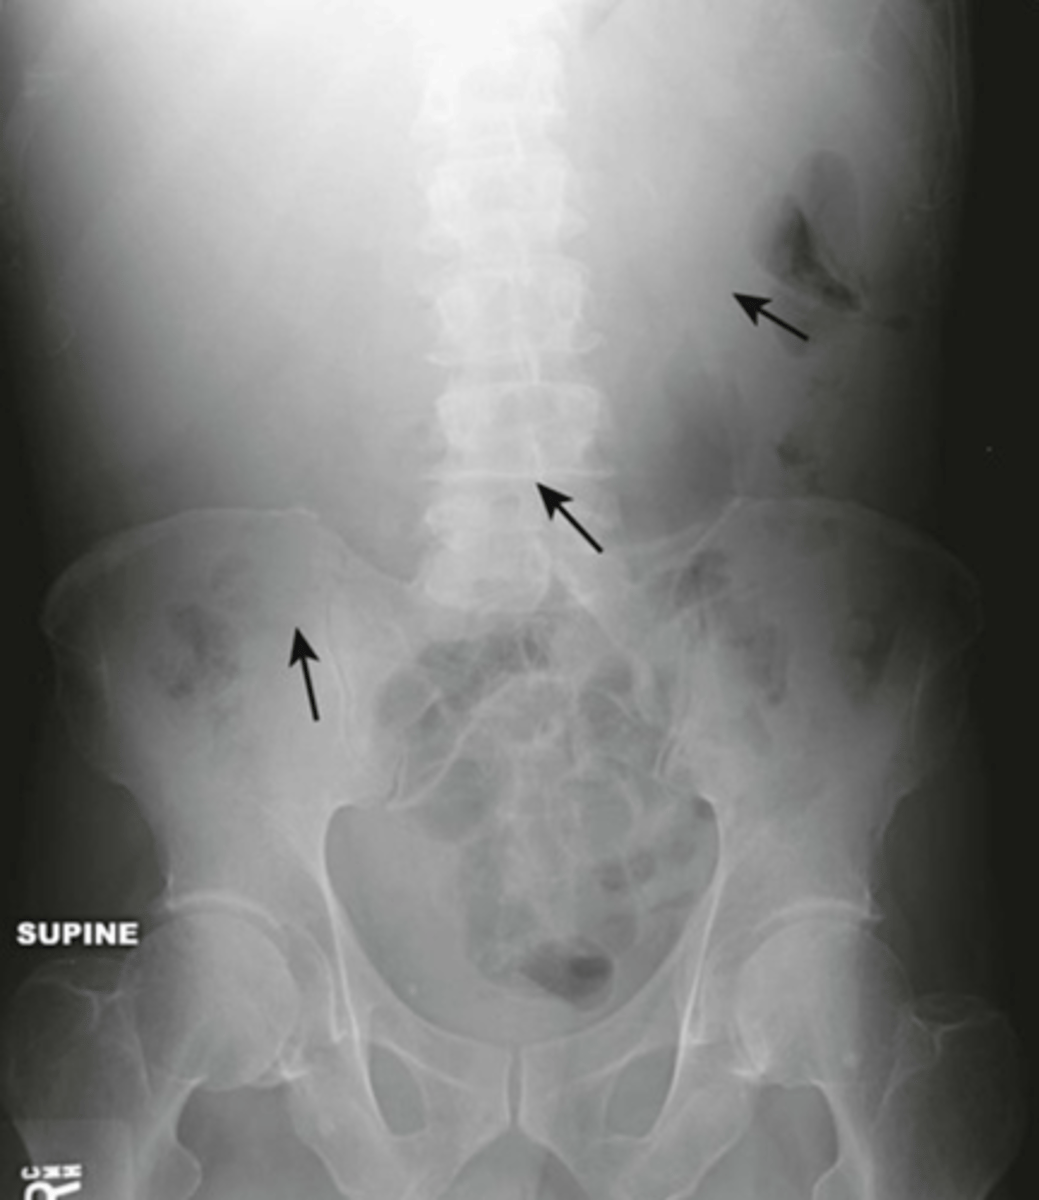

small bowel obstruction

lesion obstructs lumen, proximal to transition point bowel loops become dilated with air, distal to transition point bowel loops become decompressed, no air in rectosigmoid

SBO imaging

X-Ray shows multiple dilated bowel loops, "step ladder appearance", no or little gas in colon/rectum